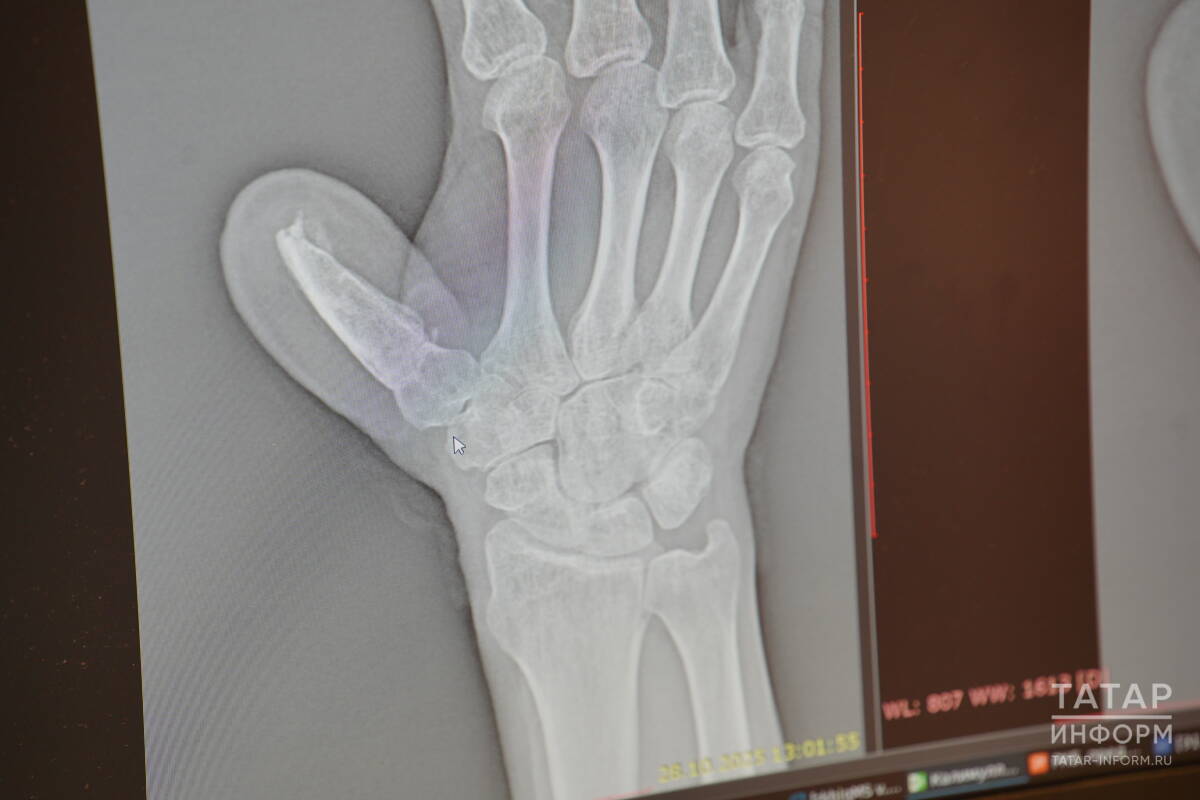

Травматолог-ортопед, микрохирург Эльвира Кадырова показала нам рентгеновский снимок пострадавшей руки и объяснила, почему палец не потерял возможность двигаться совсем.

Рентгеновский снимок пострадавшей руки

«Движение большому пальцу дают три сустава: межфаланговый, пястно-фаланговый и запястно-пястный сустав. Палец был отрублен глубоко, но остался кусок последнего сустава. Косточка, взятая с таза, срослась с суставом. Вот и получилась цельная кость большого пальца. Поэтому теперь мужчина может двигать им вверх-вниз, вправо-влево», – рассказала врач.